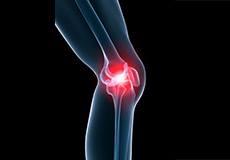

Knee Pain

Knee pain is a common condition affecting individuals of various age groups. It not only affects movement but also impacts your quality of life. An injury or disease of the knee joint or any structure surrounding the knee can result in knee pain.